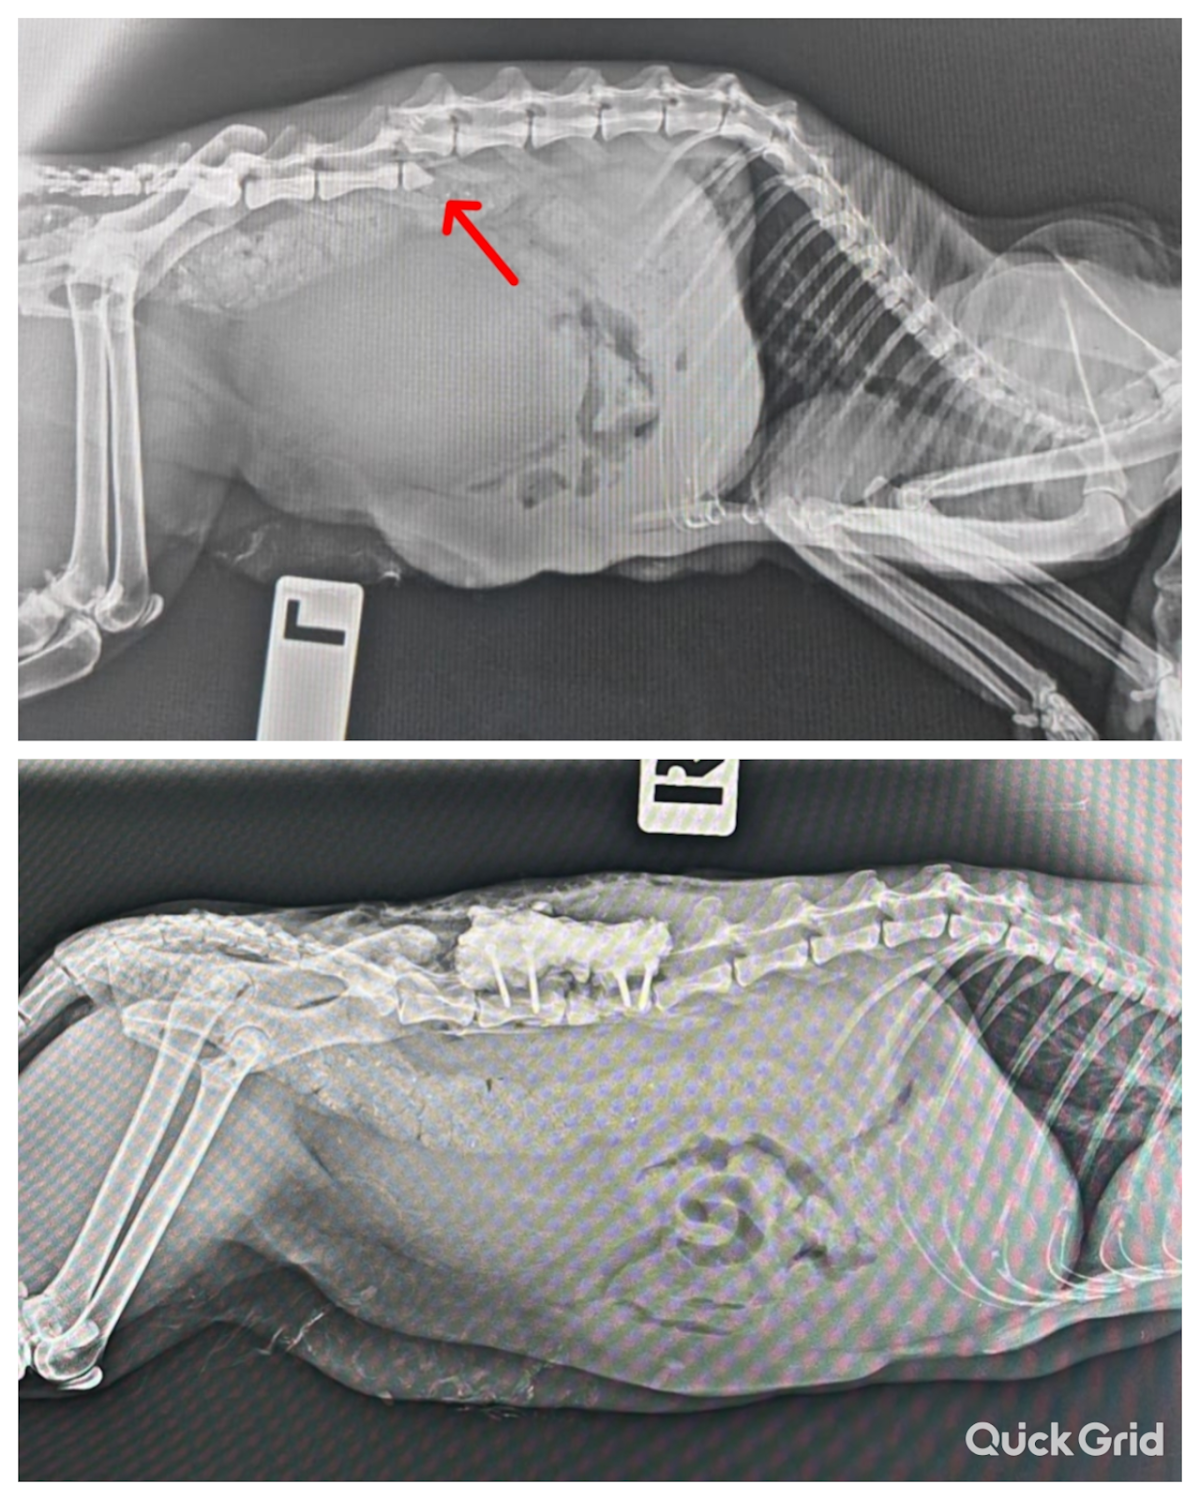

Yaklaşık 1 ay önce site bahçemizde yavru sokak kedisi buldum ,seveyim dedim koşarken arka ayağını sürüdüğünü gördüm ,yağmurlu bir havaydi çok üzüldüm.Hemen evime aldım ve ertesi gün güvenerek gittiğim yakın bir veterinere götürdüm, sağolsun ilgilendiler film çektiler kırıkları olduğunu söylediler ve ortopedi yapan Deniz pete yönlendirdiler.Ve sürecimiz başladı, operasyon öncesi 5 gün toparlanmasi için bakım yapıldı, ve operasyon başarilı geçti, 3 gün sonrasında da taburcu oldu. Taburcu sonrasi iştahi ve dışkılaması herseyi yolundaydi ve 10 gün sonra "Süslü" :) yavrumuz yürümeye başladı.😻bugün kontrol günüydü, Maşallah çooook iyi şimdi😊